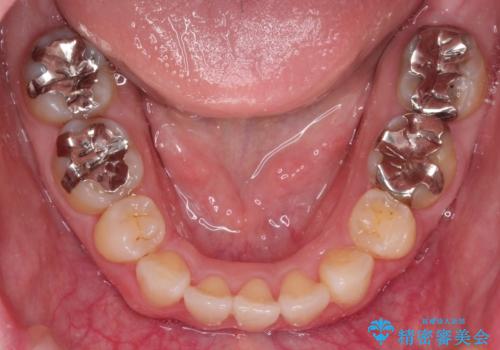

- 口が閉じずらく、口元が突出している状態でした。

上下左右の歯を1本ずつ、合計4本抜歯して、ワイヤーにて矯正することとなりました。

もともと下の前歯の永久歯が1本欠損しており、抜歯部位の選択を考慮しなければならない症例でした。シミュレーションを事前に行い、下顎の抜歯部位を決定しました。